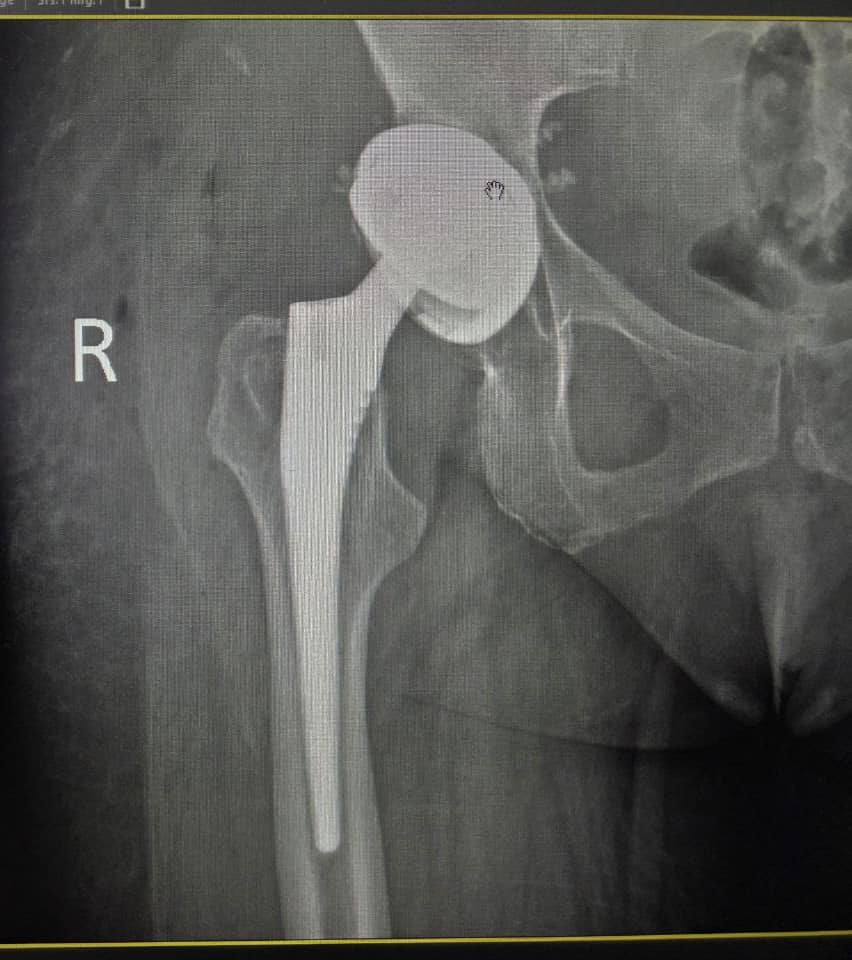

Вывих тазобедренного сустава спустя 12 лет после эндопротезирования

Удачно выполненное эндопротезирование тазобедренного сустава способно решить проблему боли и нестабильности сочленения с минимальным риском осложнений.Однако со временем риск возникновения вторичных травм (прежде всего – вывихов) увеличивается.На фото мы видим пример, когда вывих тазобедренного сустава произошёл спустя 12 лет после инсталляции эндопротеза.

Ввиду вероятности повторных вывихов, высокой интеграции части сочленения с эндопротезом, а также с целью дополнительной стабильности имплантата, было принято решение установить эндопротез тазобедренного сустава с двойной мобильностью.Такой имплантат способен минимизировать риски расшатывания вертлужной губы и обеспечит выживание сустава в 80% случаев даже через 20 лет.